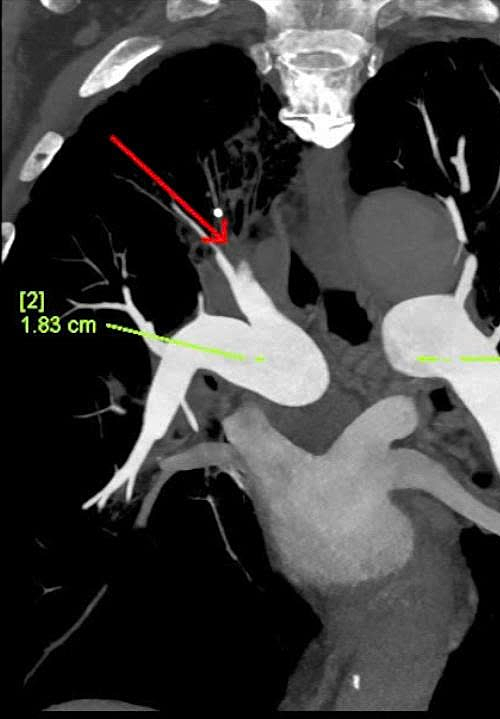

Results revealed Kien also had atherosclerotic plaques causing 50-60% narrowing of the left anterior descending artery, atherosclerosis along the aortic wall, and complete occlusion by thrombi of branches A1, A2, and the distal segment of an A3 branch of the right pulmonary artery. Doctors diagnosed him with pulmonary embolism, complicated by acute exacerbated COPD with superinfection and various cardiovascular and metabolic diseases. Untreated pulmonary embolism disrupts blood flow to the lungs, causing systemic oxygen deprivation, hypotension, arrhythmias, and cardiac arrest.

Chest CT scan revealing thrombi completely filling the lumen of multiple branches of the right pulmonary artery (red arrows). *Photo: Tam Anh General Hospital* |